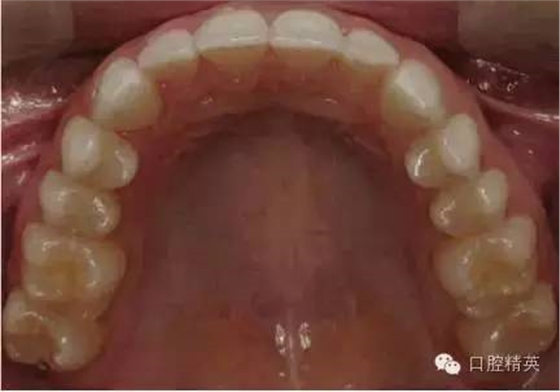

上頜合面照

合面觀

1:2 (1:3)放大倍率

需要使用拉鉤及反光板

•合面照需要使用成像清晰的反光鏡。

•請拍攝時使用拉鉤,否則軟組織會包裹鏡面阻擋牙面。

•中切牙唇面應位于相片邊緣處。

•取景時應盡量減少反光鏡邊緣和嘴唇的暴露?;颊叩谋亲踊蚍欠垂獬上竦难例X應不要位于畫面中。

•輕吹反光鏡或將反光鏡泡于溫水中能減少鏡面霧氣的形成。

•相機應位于反光鏡鏡面45°左右處。反光鏡中的成像應為牙齒的舌側及唇側都可見。一個過淺的拍照角會使得唇頰面及舌腭面的楔狀隙角度記錄有誤。

•盡量暴露所有的牙齒。至少應包括從中切牙到第二磨牙近中。前牙應始終能清晰成像。

•照片中應能清晰顯示上切牙邊緣位置、唇頰側及舌腭側楔狀隙。

•此照片可以從患者正前方拍攝(鏡頭稍向上斜),或可以直接位于病人后方而病人斜靠椅背。

•焦點位于反光鏡中的雙尖牙。

•開始先使用1:2 (1:3)放大倍率,然后調整放大倍率以拍攝上頜牙弓。